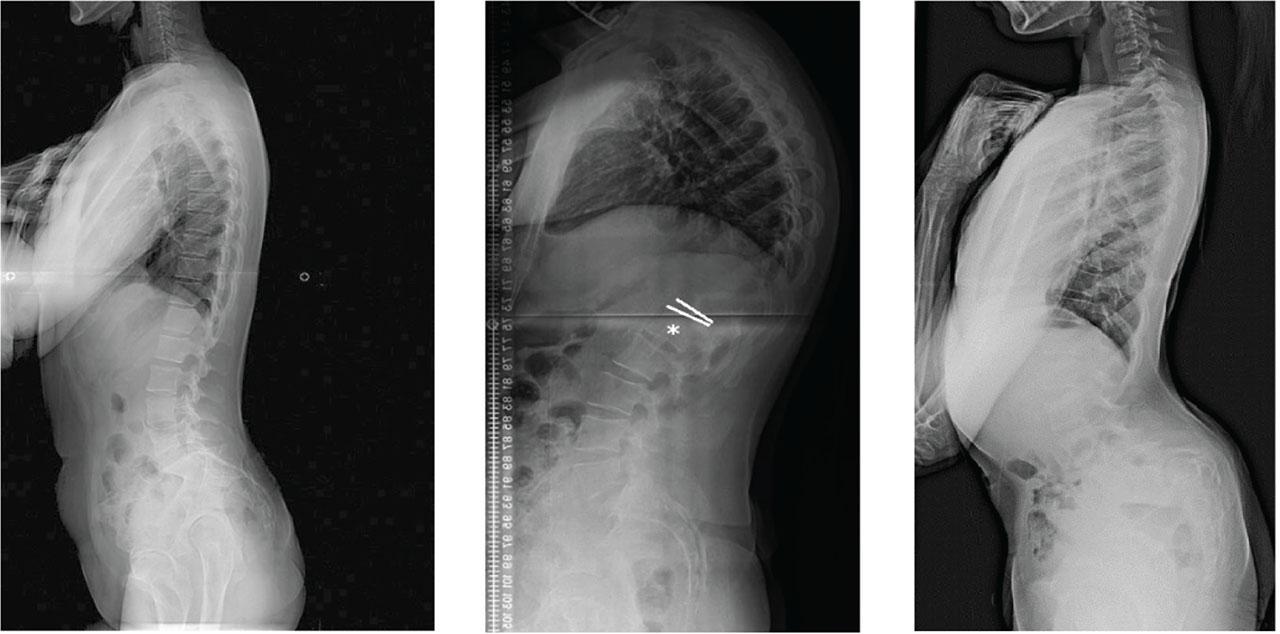

Inductive links have the tightest coupling factor when the primary and secondary coils are parallel to one another, with no angular, planar, or horizontal misalignment present. Due to the vertebral alignment of the spine, natural angle is introduced and results in angular misalignment if the transmitting coil is held parallel to the back region. Figure 10 demonstrates the natural curve of the spine, along with spinal deformities which XLIF aims to provide relief from [1].